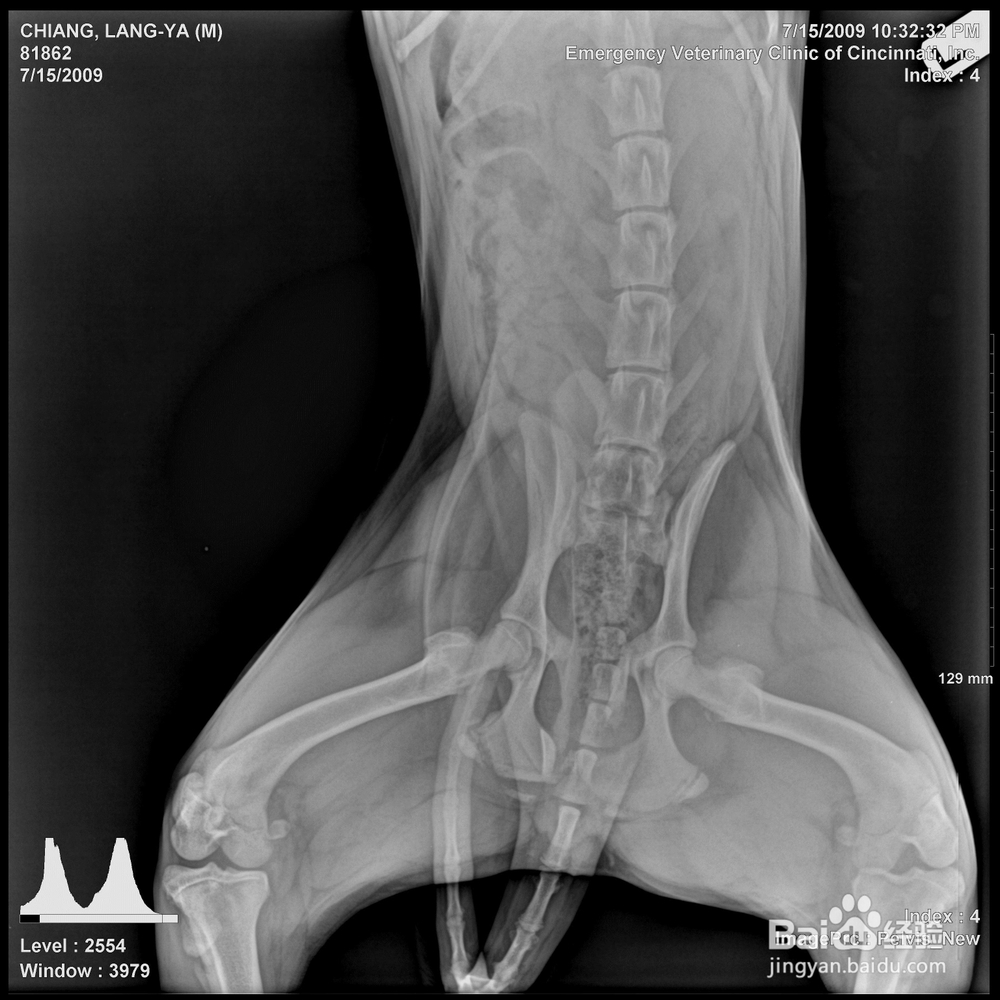

金毛、拉布拉多等常见的犬种,我们常常听到一些关于中大型犬髋关节疾病的问题,那么我们就对髋关节疾病-CHD进行进一步的了解,CHD就是犬髋关节发育不良(Hip displasia)的简称,是一种先天性疾病,多见于中大型犬只,主要特征表现为髋关节不同程度的松弛、半脱位或全脱位,最终发展为严重的退行性关节炎,这种疾病可以给犬的正常生活造成严重影响,82个以上品种的犬可以遗传本病。绝大多数患有CHD的犬在发病初期很少或根本没有明显的临床症状。一般通过X光在腹背侧骨盆处进行检查,当明显地观察到HD的特征症状时才能确诊。由于此病没有有效的治疗方法,因此,要想避免疾病的发生,需要一定的遗传基因控制。

多数犬只高发病时期在4-10个月,初期表现后肢无力,喜卧,起立困难,走路摇摆,有些幼犬可能会像兔子一样跑步,或者趴在地上四肢向后伸展。他动运动感觉关节松弛,可听到异常声音。有些犬进行触诊时可能出现麻痹现象。最终确诊需要通过X线。